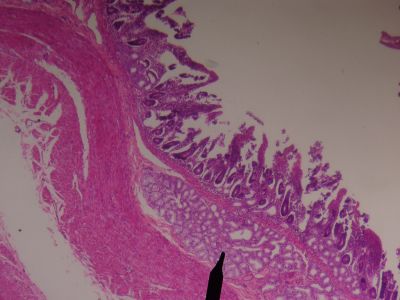

This is a histology slide of the small intestine. Note the Brunner's glands.